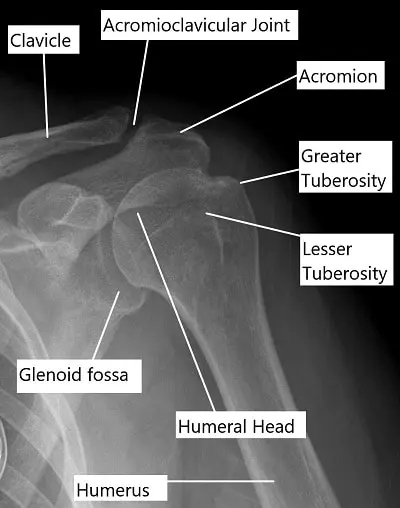

X-ray of the shoulder joint.

- X-rays are commonly used to evaluate bone injuries, including fractures or separations of the clavicle or acromion.